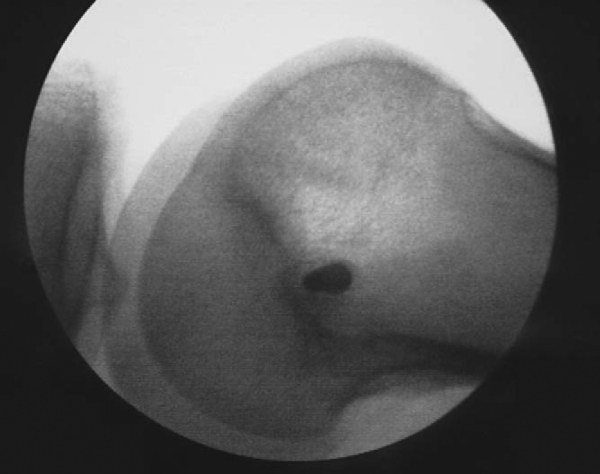

Once adequate anesthesia has been established, a comprehensive examination is performed. It is usually easier to characterize patellar stability, translation, and tilt when the patient is anesthetized. With the knee in extension, the position of the patella is determined at rest and with a lateral translation force applied (

Fig. 72-1

). Even an unstable patella will not stay dislocated unless the knee is maintained in a flexed position (